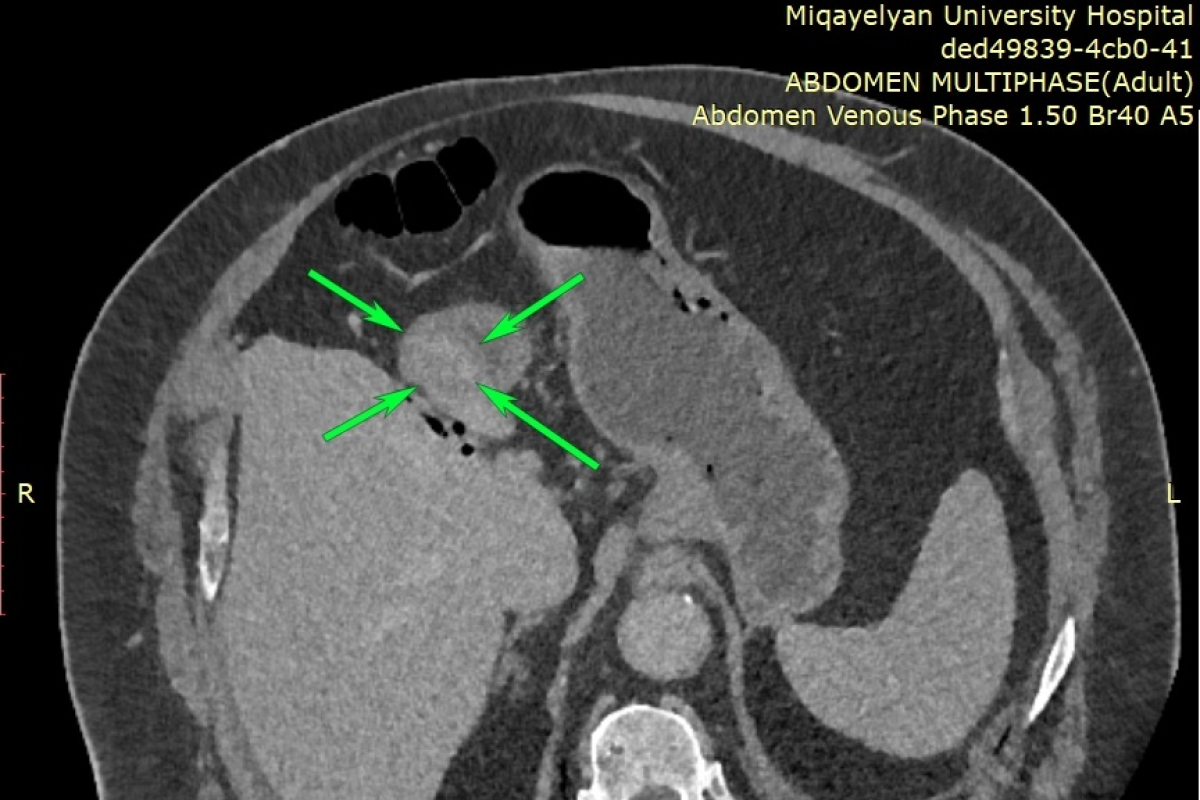

Էզոֆագոգաստրոդուոդենոսկոպիայի ժամանակ հայտնաբերվել է ստամոքսի առաջային պատի ուռուցք, որը տեղակայված էր ստամոքսաելքի շրջանում (ծառայության ղեկավար՝ Կարեն Մանուկյան): Կատարվել է նաև համակարգչային շերտագրություն կոնտրաստավորմամբ (ծառայության ղեկավար՝ Լևոն Դավթյան), որը հայտնաբերել է նշված հատվածում հստակ եզրերով ներպատային ուռուցք: